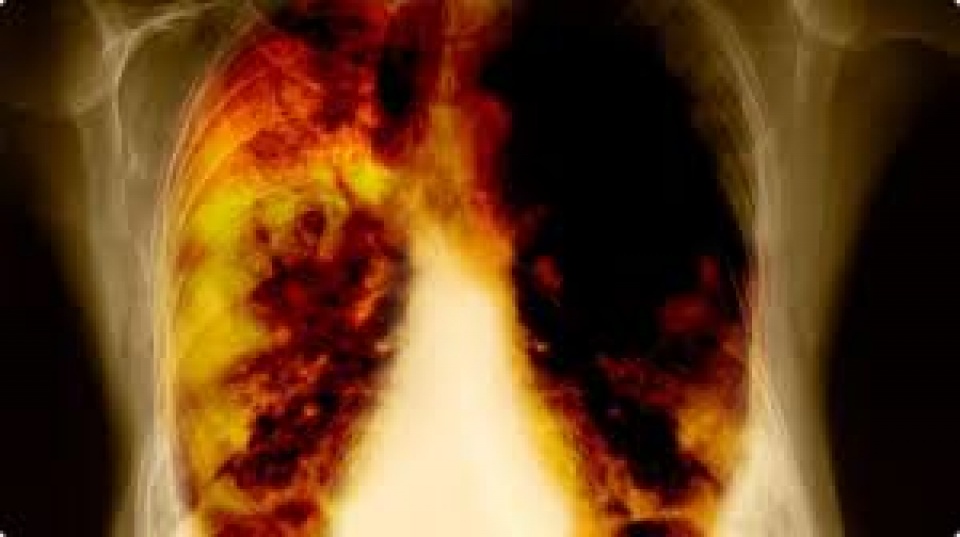

| Ung thư phổi là loại ung thư phổ biến nhất di căn lên não, với ít nhất 40% số người bị ung thư phổi di căn não. (Nguồn: Diseases Web) |